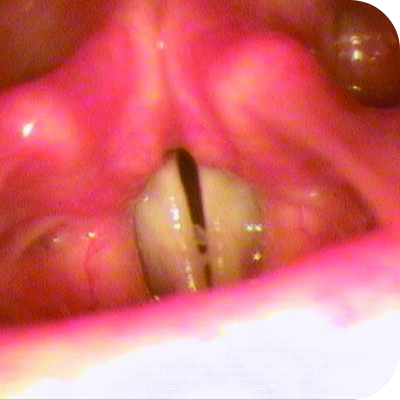

Respiratory Tract

33% of people with PLGD-1 have lesions in the respiratory tract.5

Respiratory lesions may first look like frequent pneumonia, asthma, or a cough that won’t go away. Without treatment, they can block the airway, cause a collapsed lung, or lead to trouble breathing.6

Ligneous gingivitis caused by congenital plasminogen deficiency type 1, manifesting as gum lesions Respiratory tract lesions in plasminogen deficiency type 1 patient Skin lesions on arm